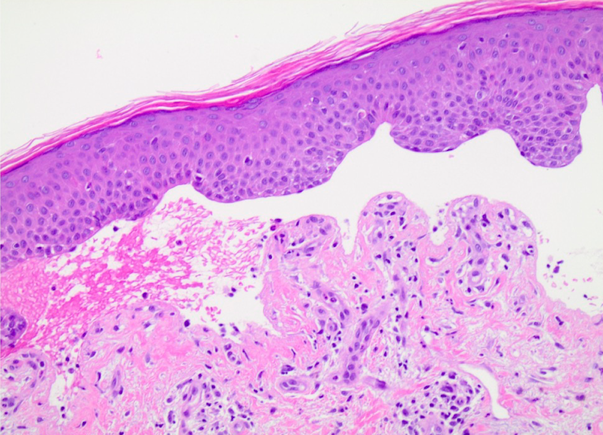

Pruritic blistering eruption on the forearms of a 60 year old male

CLINICAL HISTORY: A 62-year old male was referred to the dermatology clinic by his primary care physician (PCP) for a blistering rash on his arms. Three months prior to his presentation, he started to develop severe pruritus on his bilateral forearms. Shortly after the pruritus started, he developed large, blood-tinged blisters on his forearms. These blisters would rupture, leak fluid, and dry up. The patient saw his PCP for his blisters and they suspected a drug reaction to Lisinopril which had recently been started prior to his rash. His lisinopril was discontinued and changed to metoprolol with no change in his blisters. No topical treatments were attempted at that time. The patient has a past medical history of diabetes mellitus type 2, hypertension, and gastroesophageal reflux disease. He denied a personal or family history of hepatitis B or C, autoimmune disease, irritable bowel disease, or a history of recent travel. He has no known allergies, and his medications include metformin 500mg QD, metoprolol succinate 50mg QD, and omeprazole 40mg QD.